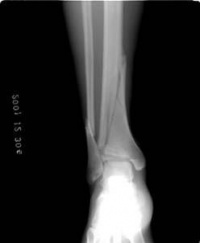

(1)儿童患肢伸入车轮扭转伤是通过间接暴力所致造成胫腓骨中下段骨折。因胫腓骨中下1/3是三棱形和四方形骨干移行部,此轴细弱为骨折好发部位。儿童在坐车的过程中,其下肢不慎伸入正在转动的车轮内,导致而身体不能随之移动,胫腓骨受到牵拉和向内弯曲,超过胫骨所能承受的负荷,造成骨折。

(2)造成踝部伸入车轮内随转速传导暴力致胫腓骨中下段骨折也符合其致伤的外力作用点和发生损伤的部位不在一起的间接暴力骨折的理论根据。

(3)对自行车车轮轧伤致胫腓骨中下段骨折漏诊病例的原因进行分析,认为主要是临床忽略了全面检查,往往被局部症状,如外表皮肤碾挫伤、出血、肿胀等所掩盖。特别是检查一个不合作的受伤儿童,没有抓住特点,找到其相应较隐蔽的骨折部位压痛点。患儿又不能得到正确提供敏锐的难以忍受的骨折部位,导致X线检查漏摄,部位错摄、少摄、造成漏诊。应值得提出的是因为胫骨干下1/3外侧穿入有营养血管,如果此处骨折伤及营养血管,漏诊时间长者或病情重者,导致的不良后果将引发不必要的医疗纠纷和医疗赔偿,给医院的信誉和经济带来一定的损失。